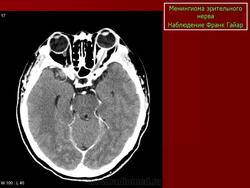

КТ-семиотика

На КТ срезах без контрастного усиления менингиома зрительного нерва выглядит изоденсной. Типично наличие линейных или точечных обызвествлений. Симптом «трамвайных рельс» отражает накопление КВ по сторонам гиподенсного зрительного нерва или наличие обызвествлений в структуре опухоли. Как правило, наиболее дистальная часть зрительного нерва, в месте его вхождения в глазное яблоко, не содержит обызвествлений.

При исследовании необходимо определить расположение бляшковидной менингиомы относительно бугорка турецкого седла и пластинки клиновидной кости, так как данный тип опухоли может распространяться интракраниально через канал зрительного нерва. КТ не позволяет адекватно визуализировать интракраниальное распространение опухоли, которое может привести к развитию двусторонней слепоты.